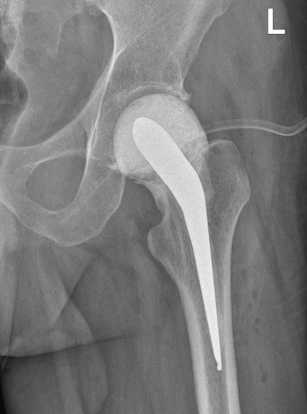

При повторной госпитализации через семь месяцев в НМИЦ ФПИ выполнена трехкратная пункция пери-имплантного пространства левого тазобедренного сустава. Роста микроорганизмов не выявлено. Перед вторым этапом эндопротезирования функциональные показатели сустава по шкале HHS — 64, по шкале WOMAC — 32, выраженность болевого синдрома по шкале ВАШ — 2 балла. 17.11.2023 произведен второй этап эндопротезирования в объеме удаления артикулирующего спейсера, тотального бесцементного эндопротезирования левого тазобедренного сустава Beijing Montagne Medical device / Zimmer (рис. 3).

Рис. 3. Рентгенограмма левого тазобедренного сустава пациента Ш. в первые сутки после операции тотального бесцементного эндопротезирования левого тазобедренного сустава Beijing Montagne Medical device / Zimmer